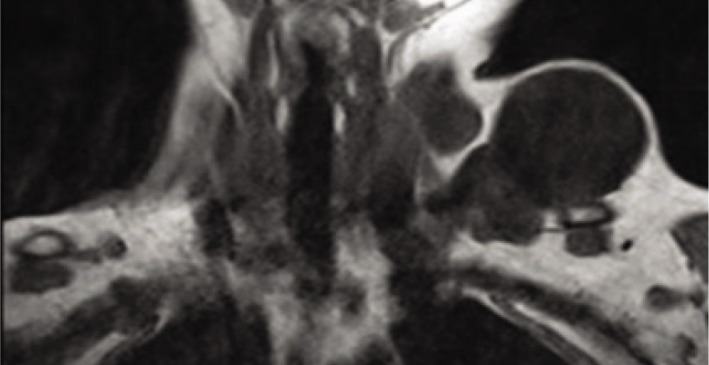

Neck cysts can be classified as congenital, infectious-inflammatory, and neoplastic. Hydatid disease is a parasitic infection caused by Echinococcus, is usually seen in the liver and lung and, is rare in the head and neck region even in endemic areas. If not treated, a life-threatening condition may be encountered. In this study, a case of hydatid cyst operated due to a cystic lesion with a diameter of approximately 8 cm in the neck was presented by reviewing the literature.